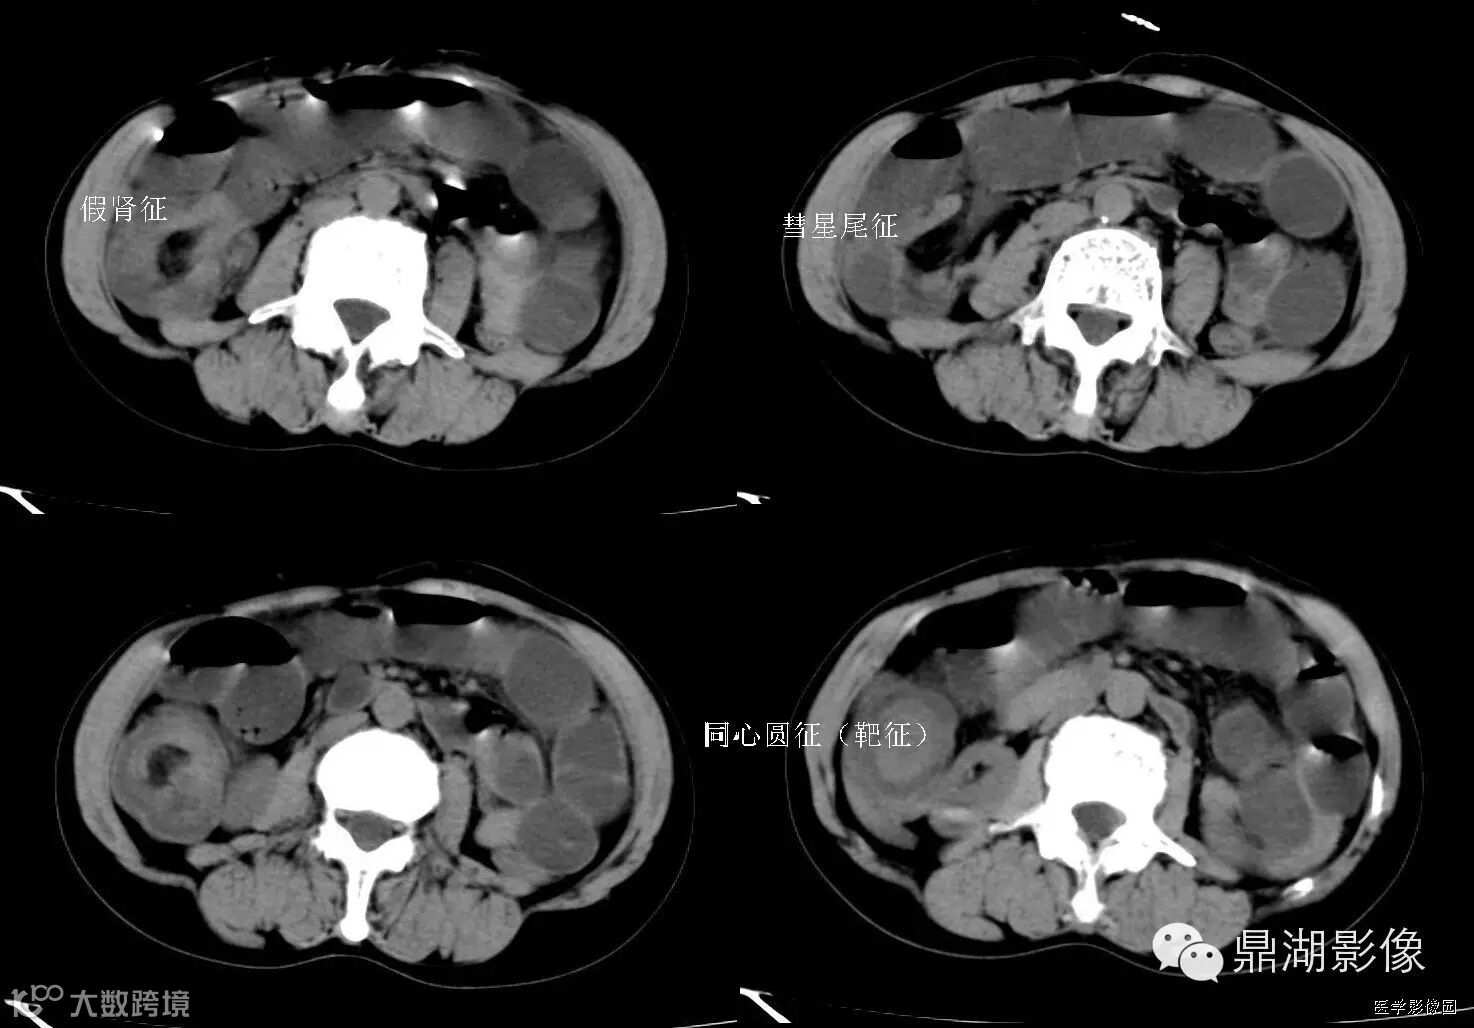

1靶征(肠套叠)

是肠套叠最常见的特征性CT征像,为肠套叠长轴与CT扫描层面垂直时的表现,反映了套叠的各层肠壁、肠腔及肠系膜间的关系。典型排列为自外向内分别代表鞘部外层肠壁、鞘部肠腔内造影剂、鞘部内层肠壁、偏心性套入部肠系膜、套入部肠壁、套入部肠腔内造影剂。

由于肠套叠长轴与CT扫描层面的角度不同,表现各异。如扫描层面和迂曲的肠道相平行时,表现为彗星尾征或肾形征:即套叠近端肠系膜血管牵拉聚拢的征象。一般情况下,彗星尾征均与肾形肿块相伴出现。该肾形肿块为套鞘部游离缘与套入部近端肠管及肠系膜的CT斜切面图像,其中游离的套鞘呈弧形围绕套入部,形状若肾轮廓外形,而套入部近端肠管、肠系膜形状若肾蒂。此时,所谓彗星尾征的组成还应包括套入近端肠管。如果套叠的肠管与CT扫描垂直,则呈靶形征,即肿块影表现为圆形或类似环形。通常在肿块内可分辨出层样结构,推测可能是继发于套入部和鞘部间的液体或是肠壁水肿造成密度对比,类似同心圆形;当套入部肠壁显著水肿坏死或套入部肿瘤周围浸润累及肠系膜,肠系膜血管及脂肪、套叠时间较长,套入部系膜血管受挤压时,静脉血液回流障碍,套入部肠壁充血水肿、变硬,形成不完全性肠梗阻,套叠以上肠管蠕动增强,可引起代偿性肠管扩张肥厚,并可见肠系膜连同其血管纠集、扭曲,形成“漩涡征”。

2靶征(肠壁)

主要见于腹部增强扫描,增后的肠壁表现为三层结构,内层和外层是高密度强化层,两者之间是低密度的中间层。

靶征出现于可导致肠壁粘膜水肿、炎症或两者同时存在的多肠管病变。其内层代表粘膜层,外层代表固有层和浆膜层,由于对比剂的强化而成高密度,中层的低密度被认为是由于粘膜下层水肿所致。靶征的出现提示粘膜和固有层、浆膜层的充血并伴有粘膜下水肿和炎症。颈静脉注射对比剂后,各层之间的密度差异在动脉早期和门脉晚期表现最为清楚,如果对比剂注入速度太慢、剂量太少以及延时超过2分钟,此征根本不出现。但是当粘膜下水肿非常严重时,CT平扫也可能出现。如果肠管内充满水而使肠管扩张时,靶征显示更为清楚。

CT扫描时,良性的肠管病变通常表现为肠壁的环形均匀性增厚,厚度从粘膜面到浆膜面一般不超过1公分,根据病因和病变严重程度的不同,偶尔可能超过1公分,但一般在2公分以内。肠壁出现靶征的病变主要见于缺血性肠病、小肠壁内出血、克隆氏病、溃疡性结肠炎、血管性疾病、感染性疾病、放射疾病和门脉高压所致肠粘膜水肿等。靶征并不是一个特异征象,但是在恶性病变中一般不出现此征,只是浸润性直肠癌是一个例外。